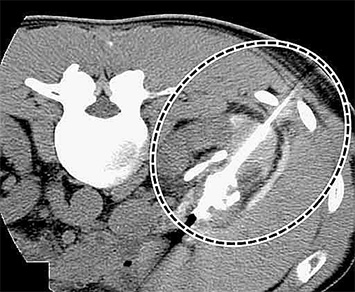

CT画像による右腎腫瘍

腎腫瘍に治療用針を刺入し凍結治療中